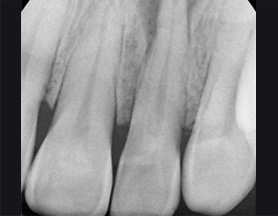

치아 뿌리 주변 염증과 치조골이 녹아내려 통증과 더불어 치아가 흔들리는 상태로 내원한 환자입니다. 우선 큐렛으로 잇몸 속 치석을 제거하였습니다. 뿌리 주변 염증은 신경관을 소독하고 약재를 삽입하는 신경치료를 시행하였습니다.

치근단 염증

신경관 소독